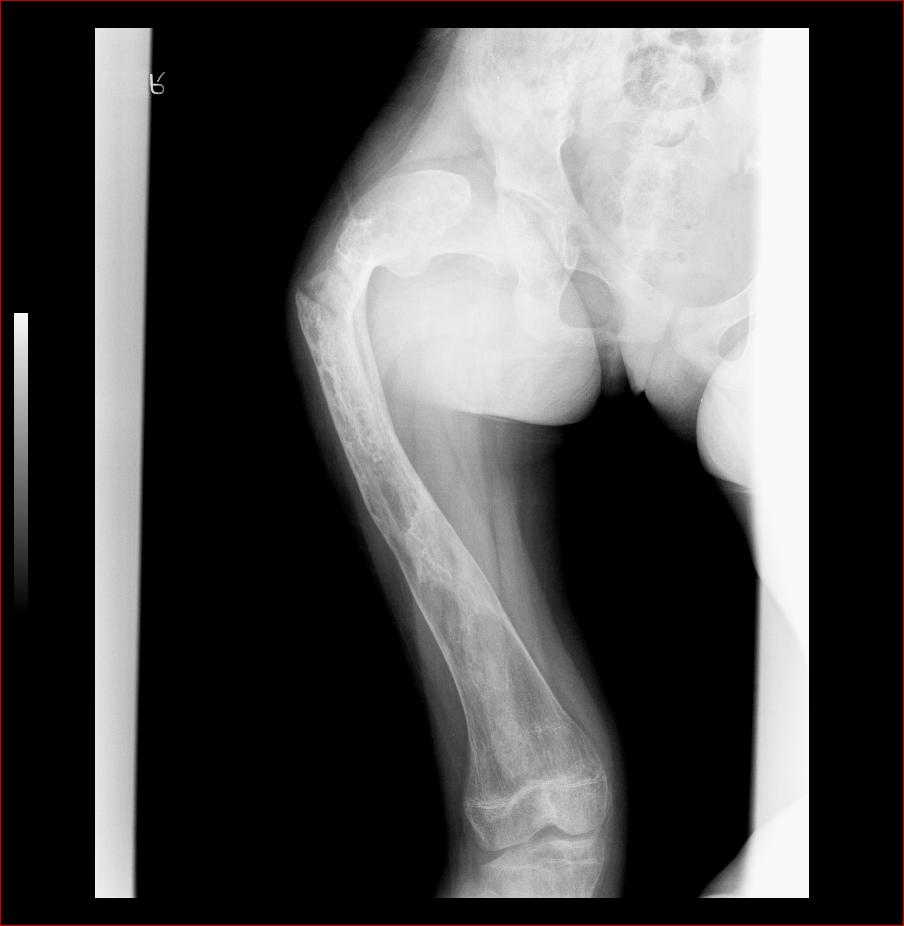

标题: X3602:F17Y,右腿畸形 [打印本页]

标题: X3602:F17Y,右腿畸形

右股骨成骨不全。

股骨藏刀样畸形改变,骨髓腔消失,骨皮质结构紊乱,典型的骨纤维异常增殖症。

股骨骨纤维异常增殖症并畸形、病理性骨折。

股骨骨纤维异常增殖症并病理性骨折。

考虑股骨骨纤维异常增殖症并病理性骨折。